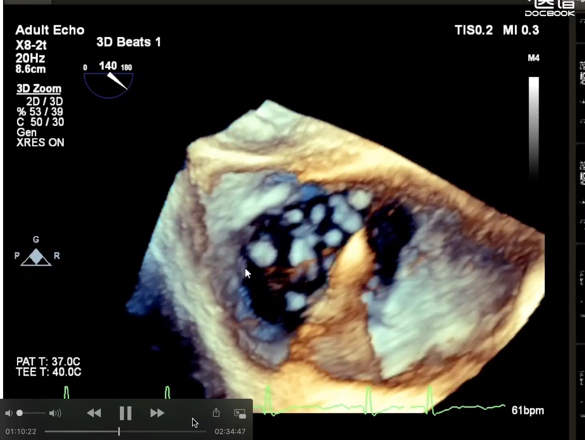

术后超声

轻中度三尖瓣反流(1~2+)。